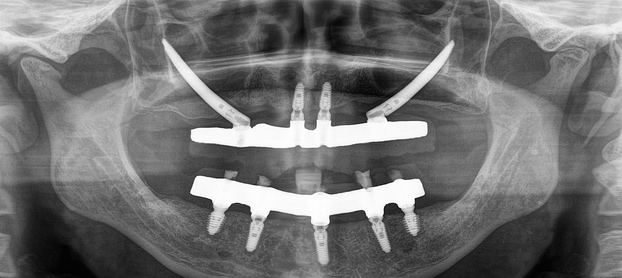

Dental Implants – Permanent Solution for Missing Teeth

Dental implants provide a reliable and long-lasting replacement for missing teeth. Using advanced technology and precise techniques like Navident dynamic navigation, Kamala Dental offers the best implant procedures that restore natural function and aesthetics, helping patients regain confidence in their smiles.